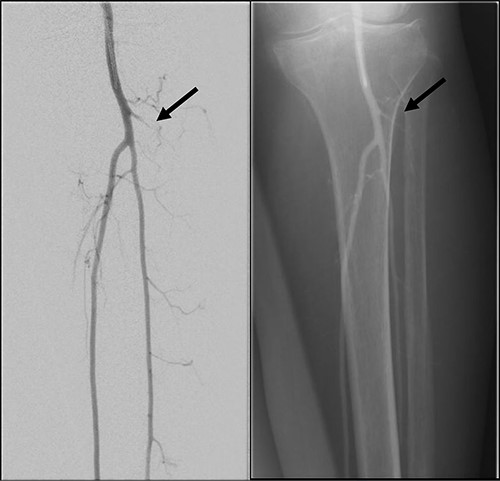

Mdm. S.N.C is a 59-year-old lady with a background of hypertension and diabetes mellitus who had corrective surgery for her left hallux valgus deformity in July 2020 (Fig. 1). This was complicated by wound dehiscence and exposure of the underlying tendon (Extensor hallucis longus) and implant (Fig. 2). An arterial duplex scan was done, which showed 70–80% occlusive disease over the proximal anterior tibial artery (ATA; Fig. 3) that likely contributed to her poor wound healing.

Illustrated diagram of left lower limb arterial duplex scan showing 70–80% occlusive disease at the proximal ATA.

Left lower limb diagnostic angiogram showing occlusion of the ATA with poor flow (arrow).